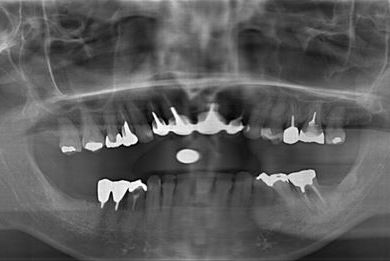

インプラントの症例写真 IMPLANT

インプラント治療+セラミック治療

| 治療内容 | インプラント3本、ジルコニアフレームオールセラミッククラウン7本(ジルコニア用土台1本)、メタルボンドセラミッククラウン3本(メタルボンド用土台3本)、ハイブリッドセラミッククラウン3本、ハイブリッドセラミックインレー3本 | ||||||||||||||||||||||||||||||||

| 治療期間 | 2年0ヶ月 |